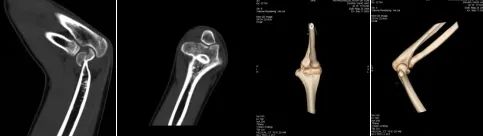

术前影像